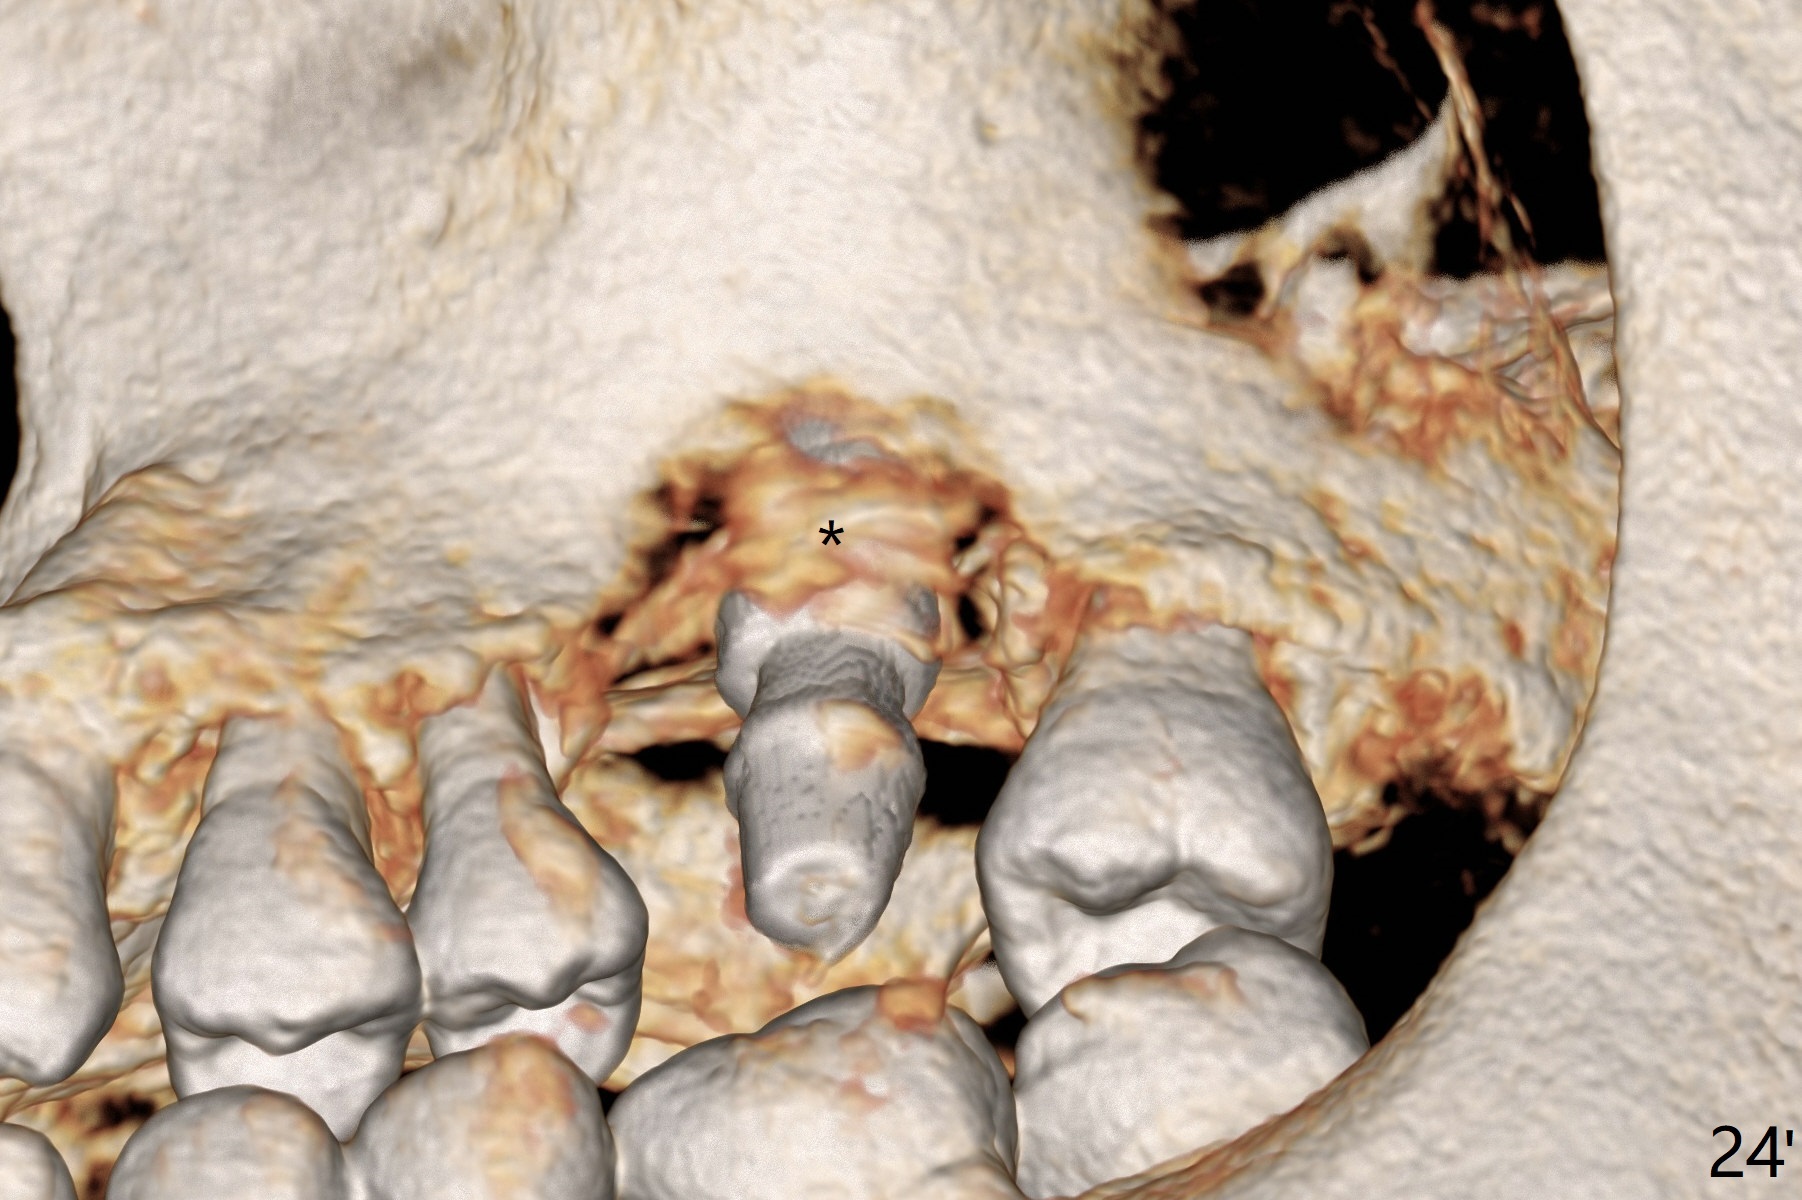

There is a mushroom around the implant nearly 5 months postop/immediately before cementation (Fig.21).  The bone density around the implant is low (Fig.22-24' *).